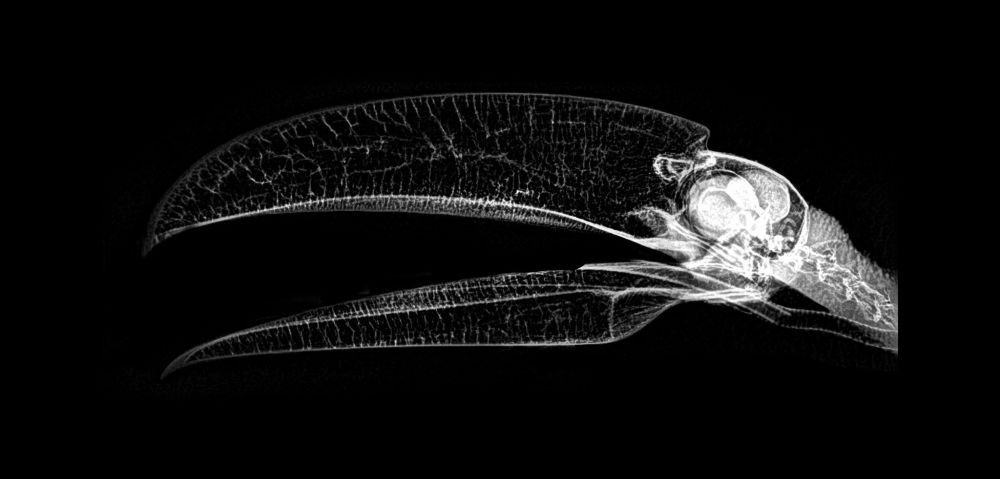

ABD'nin Oregon eyaletinde bulunan bir hayvanat bahçesi, hayvanların rutin sağlık kontrolleri sırasında çekilen X-Ray görüntülerini paylaştı.

Sağlık kontrolleri sırasında bazı hayvanlara röntgen çektiklerini söyleyen hayvanat bahçesi yetkilileri, bu yöntem sayesinde sağlık değerlendirmelerinin daha kolay yapıldığını ifade etti.

Baykuşun X-Ray görüntüsü.